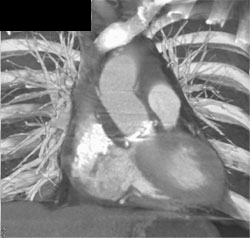

Multiple Views of Aortic Valve Replacement- Aortic Valve Replacement (AVR)- and Use of Optimal Imaging Phase